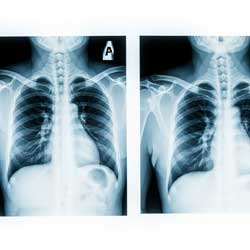

Рентген — самый распространенный и доступный метод диагностики. С его помощью можно быстро оценить состояние легочных полей, корней легких, расположение и размеры сердца, состояние плевры.

Рентген удобен как для первичного осмотра, так и для динамического наблюдения. Однако метод имеет ограничения: он не выявляет мелкие очаги воспаления или небольшие опухоли, а некоторые заболевания могут маскироваться под норму. Поэтому при сомнениях назначают более точные методы.

На практике рентгенография чаще всего используется как первый этап диагностики.